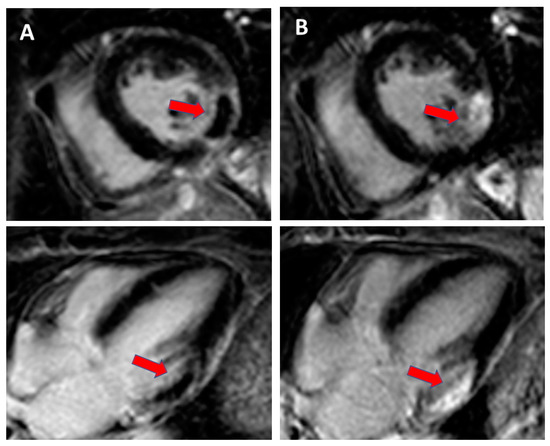

- Vago, H.; Czimbalmos, C.; Papp, R.; Szabo, L.; Toth, A.; Dohy, Z.; Csecs, I.; Suhai, F.; Kosztin, A.; Molnar, L.; et al. Biventricular pacing during cardiac magnetic resonance imaging. Europace 2020, 22, 117–124. [Google Scholar] [CrossRef] [PubMed]